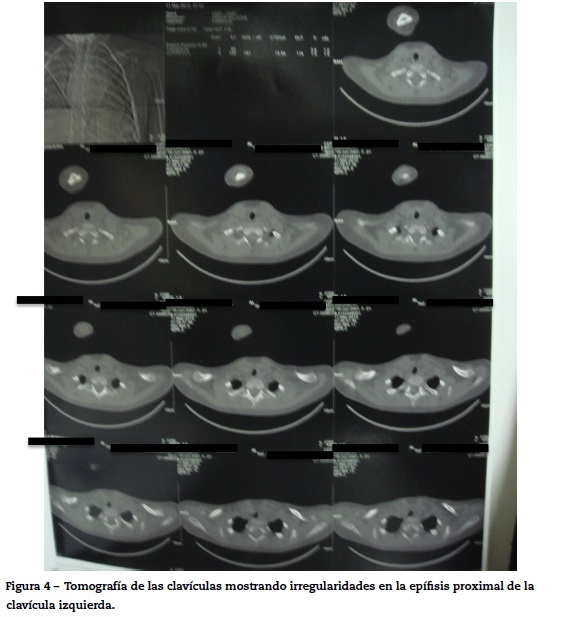

Después de 6 meses fue realizada tomografía de las clavículas sin contraste, que evidenció irregularidad de la epífisis proximal de la clavícula derecha, asociada a discreto alargamiento del espacio articular esternoclavicular correspondiente (fig. 4).